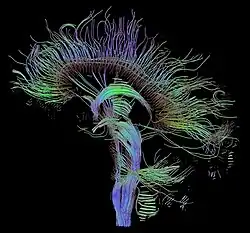

L’architecture des axones en faisceaux parallèles, ainsi que leur couche de myéline, facilite la diffusion des molécules d’eau le long de leur axe. La direction des fibres est donc la direction de plus grande diffusivité, indiquée par le vecteur propre associé à la plus grande valeur propre du tenseur de diffusion. Des algorithmes de suivi de fibres (fiber tracking) peuvent être utilisés pour reconstruire le trajet d'un faisceau de fibres nerveuses sur toute sa longueur, par exemple du cortex moteur à la moelle épinière pour le faisceau cortico-spinal (qui transmet l'information motrice).

L’IRM de diffusion est à ce jour la seule technique qui permet d’observer la connectivité cérébrale in vivo de manière non invasive. Elle est donc utilisée aussi bien dans des études sur l’animal que sur l’homme et apporte beaucoup aux neurosciences, notamment en complément de l’IRM fonctionnelle.